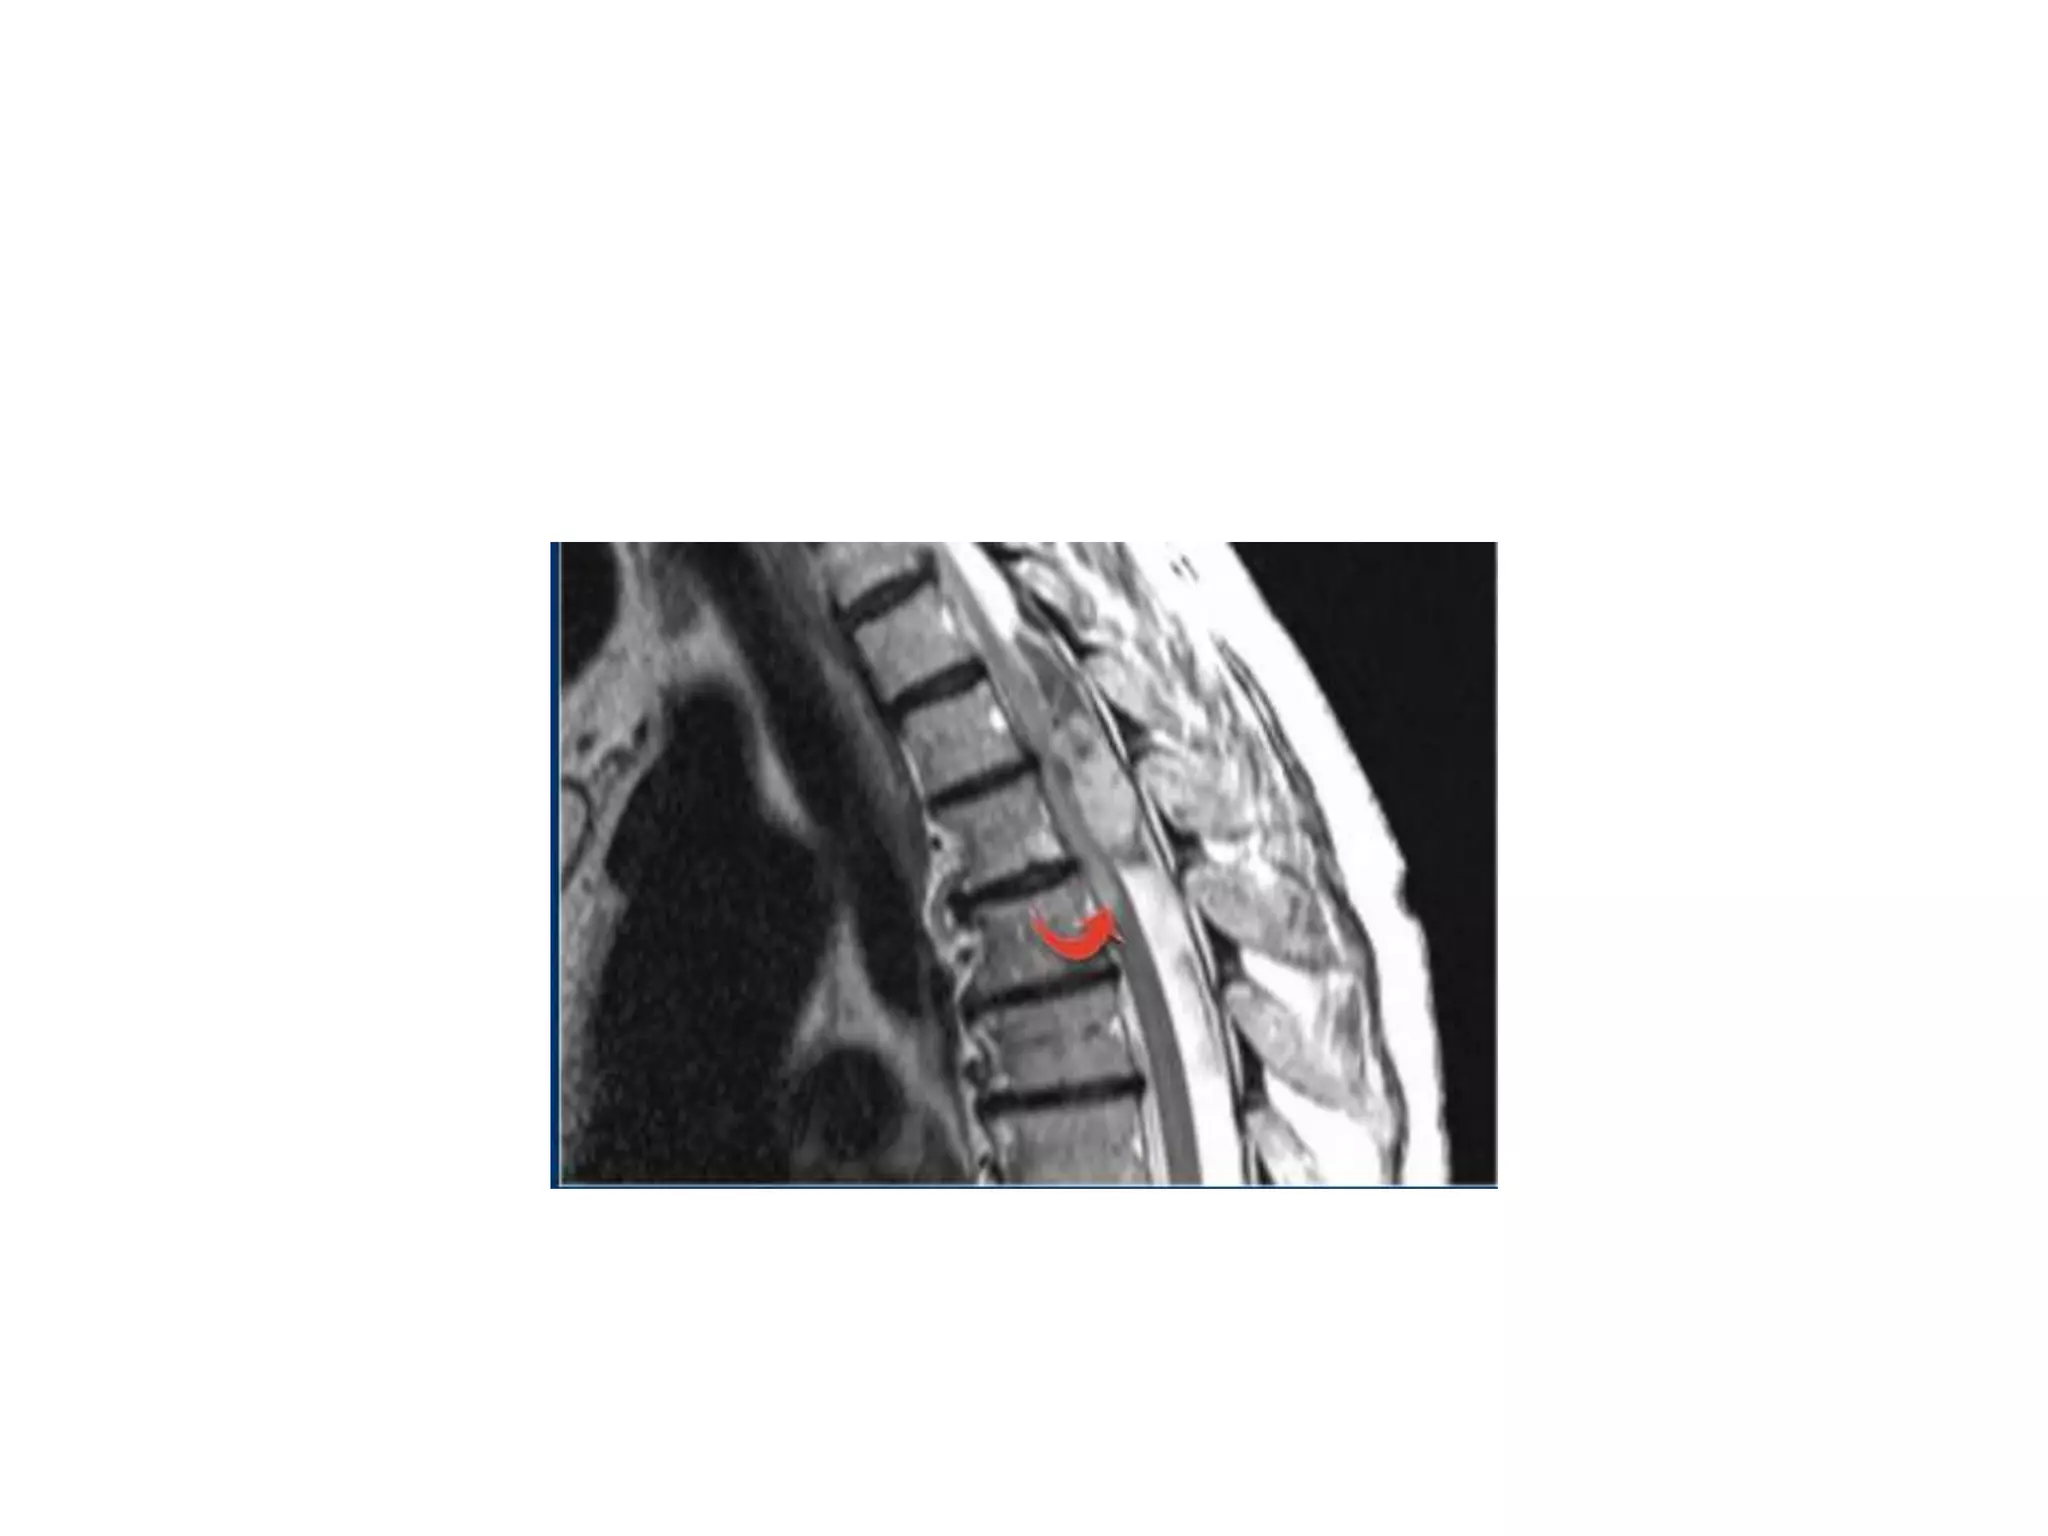

Sagg T1W image : diffuse cord atrophy in mid thorasic level

T2W image of different patient : Focal Hyperintensity in cord

predominantly posteriorly.